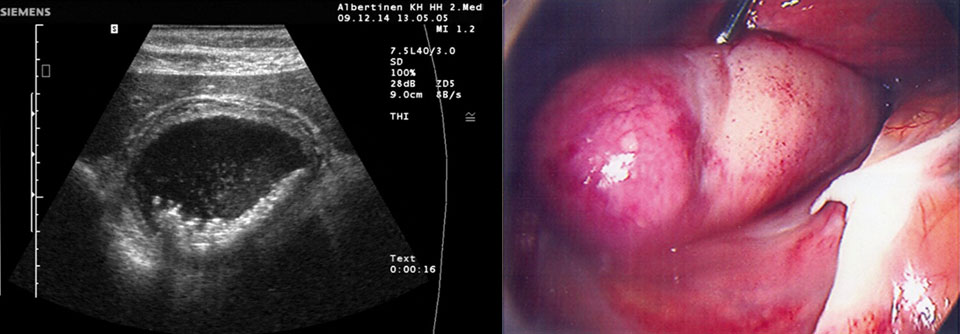

Bei sym­ptomatischen Gallensteinen war früher klar: Die Steine gehören entfernt­. Neuere Studien­ergebnisse lassen an diesem Vorgehen Zweifel aufkommen.

Sollten Erwachsene mit unkomplizierter symptomatischer Cholezystolithiasis grundsätzlich unters Messer? Eher nicht, schreiben Dr. Irfan­ Ahmed­ vom Department of Surgery des NHS Grampian in Aberdeen und seine Kollegen. Die Mediziner nahmen 434 Patienten mit unkompliziertem symptomatischen Gallensteinleiden in eine randomisierte Studie auf und wiesen sie nach dem Zufallsprinzip einer von zwei Gruppen zu. 217 Kranke sollten sich sofort einer laparoskopischen Cholezystektomie unterziehen (Gruppe 1), die übrigen 217 erhielten je nach Beschwerden eine konservative Therapie, etwa Analgetika und/oder Spasmolytika. Außerdem bekamen sie eine Patientenbroschüre mit Empfehlungen zu Maßnahmen für den…